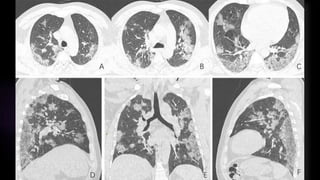

Lóbulo superior derecho: 50% (03 ptos)

Lóbulo medio derecho: 30% (03 ptos)

Lóbulo inferior derecho: 60% (04 ptos)

Lóbulo superior izquierdo: 60% (04 ptos)

Lóbulo inferior izquierdo: 80% (05 ptos)

Puntuación: 19 ptos

CONCLUSIÓN: AFECCIÓN SEVERA

CONCLUSIÓN: AFECCIÓN SEVERA –

CATEGORIA B (PATRÓN EMPEDRADO)